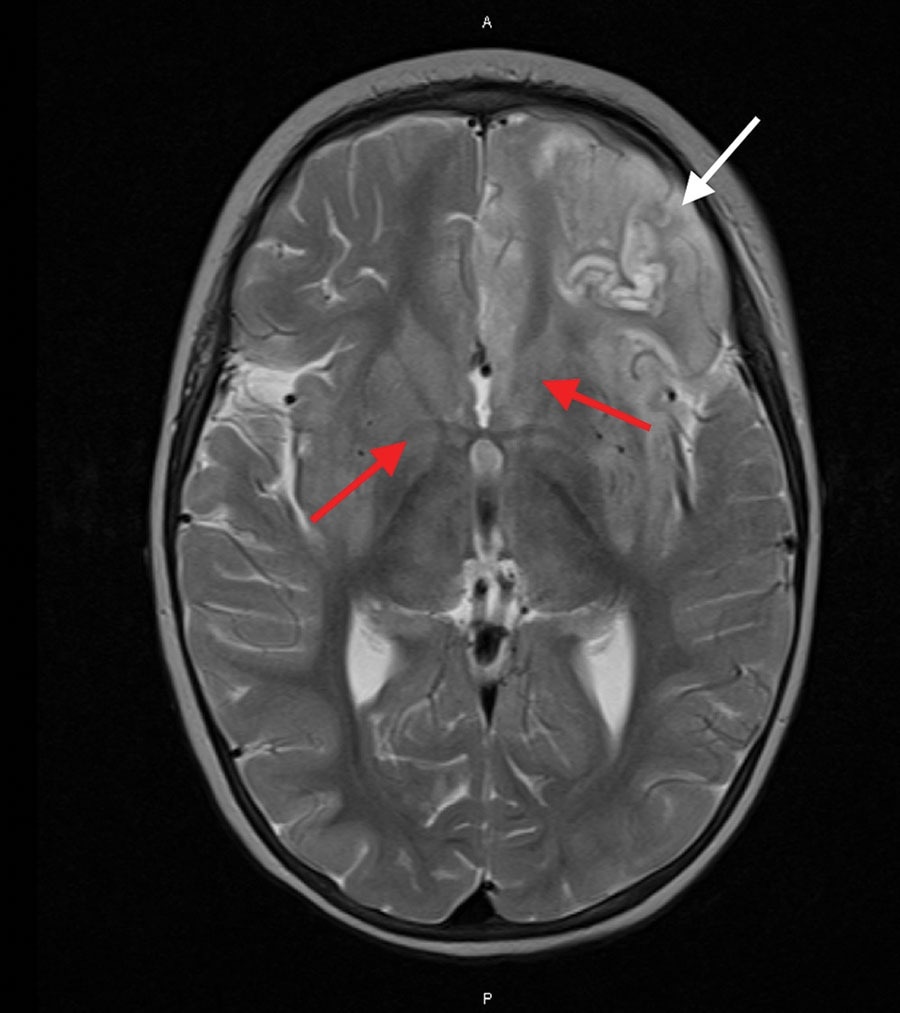

Magnetic resonance imaging of the brain of an immunocompromised child with avian paramyxovirus type 1 infection, Australia. Image, captured 16 days after hospital admission, shows predominantly left frontal and insular T2 signal hyperintensity evolving into laminar necrosis (white arrow) and hyperintensity of deep gray-matter structures (red arrows)

The patient’s condition failed to improve despite treatment with immunomodulators, antimicrobials, antiseizure drugs, and being on a ketogenic diet. An MRI taken after two weeks displayed advancing and diffuse inflammatory alterations, characterized by escalating hyperintensity in the left frontal and insular T2 signals, progressing to laminar necrosis. Additionally, T2 hyperintensity was observed in deep gray-matter structures.